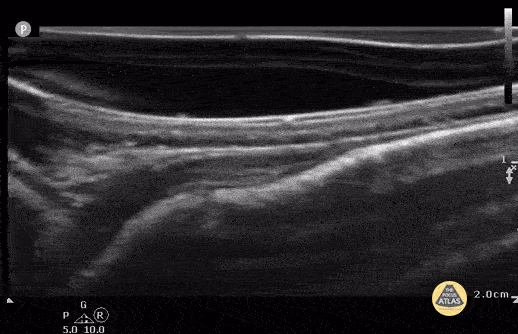

4 week old with non displaced parietal fracture using water filled glove as stand off. (Case Series 1/2) Contributor: Antonio Riera, MD